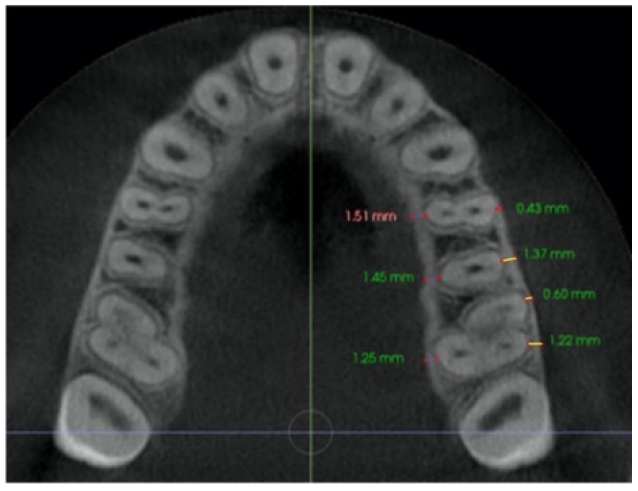

| Buccal bone thickness (BBT) | Distance from the external border of the buccal cortical plate to the center of buccal aspect of first and second premolar root, and from the external border of buccal cortical plate to the center of the messiobuccal and distobuccal root of first molar, in an axial section parallel to the palatal plane, at the level of the first molar right (R) and left (L) trifurcation for each side. | ![]() ![]() |

| Palatal bone thickness (PBT) | Distance from the external border of palatal cortical plate to the center of palatal aspect of first and second premolar root, and first molar palatal root, in an axial section parallel to palatal plane, at the level of the first molar right (R) and left (L) trifurcation for each side. | ![]() ![]() |